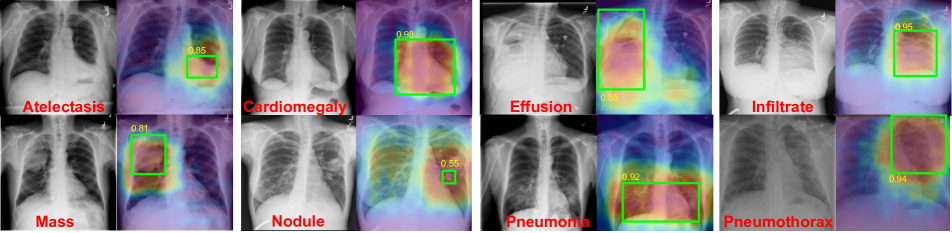

Refer to caption

Figure 5: Examples of localization results on 8 diseases along with ground truth bounding box annotations. In each pair, a chest radiograph (left) inputs into our model and the corresponding heatmap (right) is generated. The heatmaps produced from our model match with the ground-truth bounding boxes (green) annotated by radiologists and indicated good IoU results (yellow).

We generated our predicted bounding boxes by applying a naive thresholding (T=0.10.7𝑇0.1similar-to0.7T=0.1\sim 0.7) on the normalized heatmap with value ranged from 0 to 1 that obtained from our class-wise pooling layer. Examples are shown in Figure 5. No localization annotation was used during training process. The heatmaps were generated by our network with training only from image-level labels. All 880 images with bounding boxes ground truth were used for evaluation.